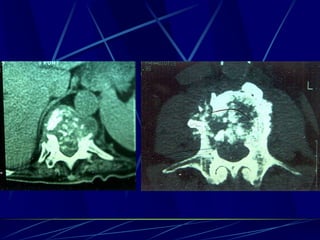

Φυματίωση της σπονδυλικής στήλης